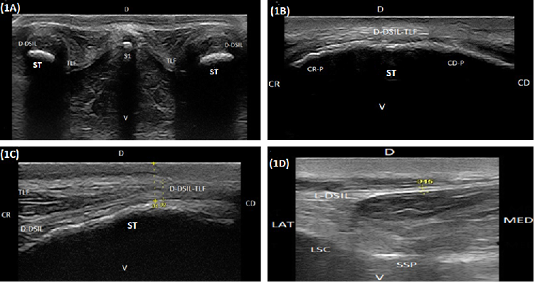

(A) Compound transverse sonogram (10 MHz linear tendon probe, 6 cm depth) at the dorsal aspect of the sacroiliac region of a 6-year-old cow showing sacral tuber (ST), the thoracolumbar fascia (TLF), the dorsal portion of the dorsal sacroiliac ligament (D-DSIL). first sacral spinous process (S1), dorsal direction (D) and ventral direction. (B) Compound longitudinal sonogram (14 MHz linear tendon probe, 5cm depth) at the dorsal area of sacral tuber of a 7- year- old cow showing sacral tuber (ST), the dorsal portion of the dorsal sacroiliac ligament- thoracolumbar fascia combination (D-DSIL-TLF), cranial margin of sacral tuber (CR-P), caudal margin of sacral tuber (CD.P), cranial direction (CR), caudal direction (CD), dorsal direction (D) and ventral direction (V). (C) Compound longitudinal sonogram at the dorsal area of sacral tuber of the same animal in Figure. 1B. showing the dorsal aspect of the dorsal sacroiliac ligament (D-DSIL), thoracolumbar fascia (TLF), sacral tuber (ST), cranial direction (CR), caudal direction (CD), dorsal direction (D) and ventral direction (V). (D) Transverse sonogram (10 MHz linear tendon probe, 6 cm depth) of an 8-year-old cow showing the lateral aspect of the dorsal sacroiliac ligament (L-DSIL), the lateral sacral crest (LSC), the sacral spinous process (SSP), lateral direction (LAT), medial direction (MED), dorsal direction (D) and ventral direction (V).(A) Compound transverse sonogram (10 MHz linear tendon probe, 6 cm depth) at the dorsal aspect of the sacroiliac region of a 6-year-old cow showing sacral tuber (ST), the thoracolumbar fascia (TLF), the dorsal portion of the dorsal sacroiliac ligament (D-DSIL). first sacral spinous process (S1), dorsal direction (D) and ventral direction. (B) Compound longitudinal sonogram (14 MHz linear tendon probe, 5cm depth) at the dorsal area of sacral tuber of a 7- year- old cow showing sacral tuber (ST), the dorsal portion of the dorsal sacroiliac ligament- thoracolumbar fascia combination (D-DSIL-TLF), cranial margin of sacral tuber (CR-P), caudal margin of sacral tuber (CD.P), cranial direction (CR), caudal direction (CD), dorsal direction (D) and ventral direction (V). (C) Compound longitudinal sonogram at the dorsal area of sacral tuber of the same animal in Figure. 1B. showing the dorsal aspect of the dorsal sacroiliac ligament (D-DSIL), thoracolumbar fascia (TLF), sacral tuber (ST), cranial direction (CR), caudal direction (CD), dorsal direction (D) and ventral direction (V). (D) Transverse sonogram (10 MHz linear tendon probe, 6 cm depth) of an 8-year-old cow showing the lateral aspect of the dorsal sacroiliac ligament (L-DSIL), the lateral sacral crest (LSC), the sacral spinous process (SSP), lateral direction (LAT), medial direction (MED), dorsal direction (D) and ventral direction (V).